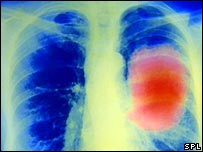

Cientistas testam vacina para câncer de pulmão

Tratamento com vacina poderia ser usado em diversos tipos de câncer

Cientistas começaram a testar, em larga escala, uma vacina contra o câncer de pulmão mais comum.

A vacina tem efeito sobre o câncer de pulmão de não-pequenas células, que cresce e se espalha mais lentamente que o outro tipo – de pequenas células – e compreende cerca de 80% dos casos tratados na literatura médica.